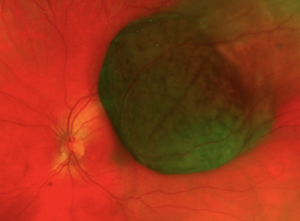

•Angle closure by shifting the iris/lens diaphragm forward as can occur with retinal tumors, choroidal tumors (Figure 1) and ring melanomas.